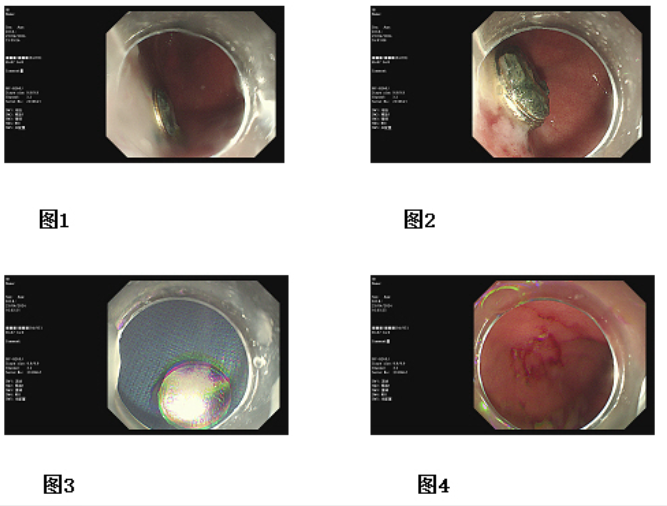

在麻醉科的通力配合下,消化內(nèi)科陳欣主任親自手術(shù)。陳主任使用一次性取石網(wǎng)籃網(wǎng)套住胃底紐扣電池,輕輕上移,這個過程不能有一點閃失,紐扣電池一旦落入腸腔,必須進(jìn)行開腹手術(shù)。紐扣電池胃里停留時間越長,堿性液泄露的可能性越大,一旦泄露,對食管、胃的腐蝕,將影響孩子的終身。5分鐘的操作,陳主任將紐扣電池成功脫出口腔,堿性液一點未滲漏,患兒化險為夷。